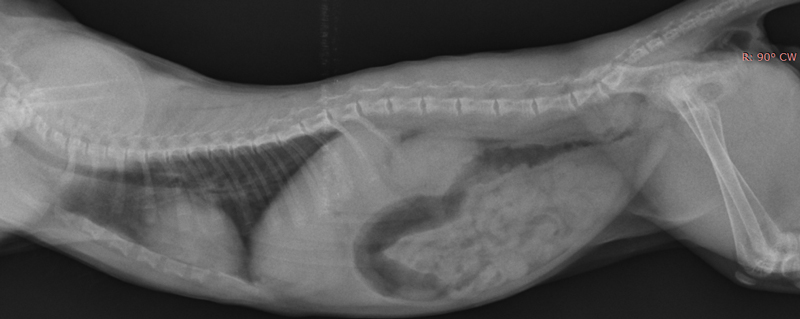

Истончение костей у кошек: причины и решения